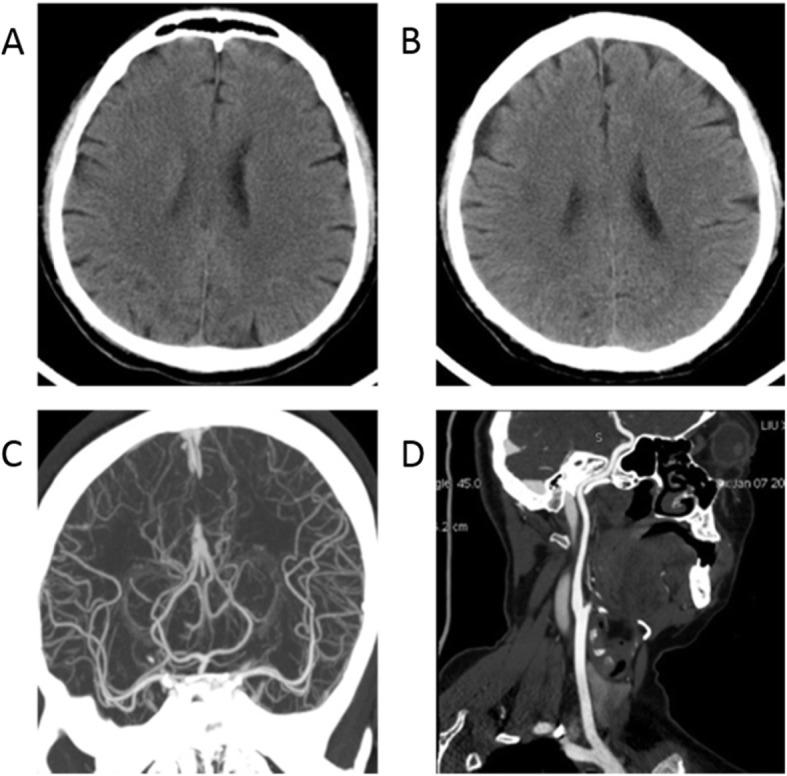

We here report two cases of coronavirus-infected pneumonia with acute ischemic stroke in middle-aged patients. In both COVID-19 cases, neurological physical examinations showed normal results before infection. Lymphocytopenia, accompanied by elevated cytokines and D-dimers, were found from serum clinical laboratory examination at admission. Dysarthria and limb muscle weakness are initial manifestations, occurring one week after infect-causative pathogen, SARS-CoV-2. The head CT and head/neck arterial CTA showed small-vessel occlusion. The patients were diagnosed with coronavirus diseases with secondary acute ischemic stroke. They were treated with tirofiban and followed up with daily aspirin and atorvastatin.

These cases suggested that secondary ischemic stroke, mainly manifested as small-vessel occlusion, should be considered for COVID-19 patients and diagnosed and treated promptly.